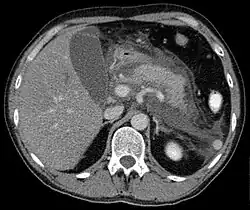

Computed tomography

Regarding the need for computed tomography, practice guidelines state:

CT is an important common initial assessment tool for acute pancreatitis. Imaging is indicated during the initial presentation if:

- the diagnosis of acute pancreatitis is uncertain

- there is abdominal distension and tenderness, fever >102 F (38,9 C), or leukocytosis

- there is a Ranson score > 3 or APACHE score > 8

- there is no improvement after 72 hours of conservative medical therapy

- there has been an acute change in status: fever, pain, or shock

CT is recommended as a delayed assessment tool in the following situations:

- acute change in status

- to determine therapeutic response after surgery or interventional radiologic procedure

- before discharge in patients with severe acute pancreatitis

Abdominal CT should not be performed before the first 12 hours of onset of symptoms as early CT (<12 hours) may result in equivocal or normal findings.

CT findings can be classified into the following categories for easy recall:

- Intrapancreatic – diffuse or segmental enlargement, edema, gas bubbles, pancreatic pseudocysts and phlegmons/abscesses (which present 4 to 6 wks after initial onset)

- Peripancreatic / extrapancreatic – irregular pancreatic outline, obliterated peripancreatic fat, retroperitoneal edema, fluid in the lessar sac, fluid in the left anterior pararenal space

- Locoregional – Gerota's fascia sign (thickening of inflamed Gerota's fascia, which becomes visible), pancreatic ascites, pleural effusion (seen on basal cuts of the pleural cavity), adynamic ileus, etc.

The principal value of CT imaging to the treating clinician is the capacity to identify devitalized areas of the pancreas which have become necrotic due to ischaemia. Pancreatic necrosis can be reliably identified by intravenous contrast-enhanced CT imaging,[22] and is of value if infection occurs and surgical or percutaneous debridement is indicated.